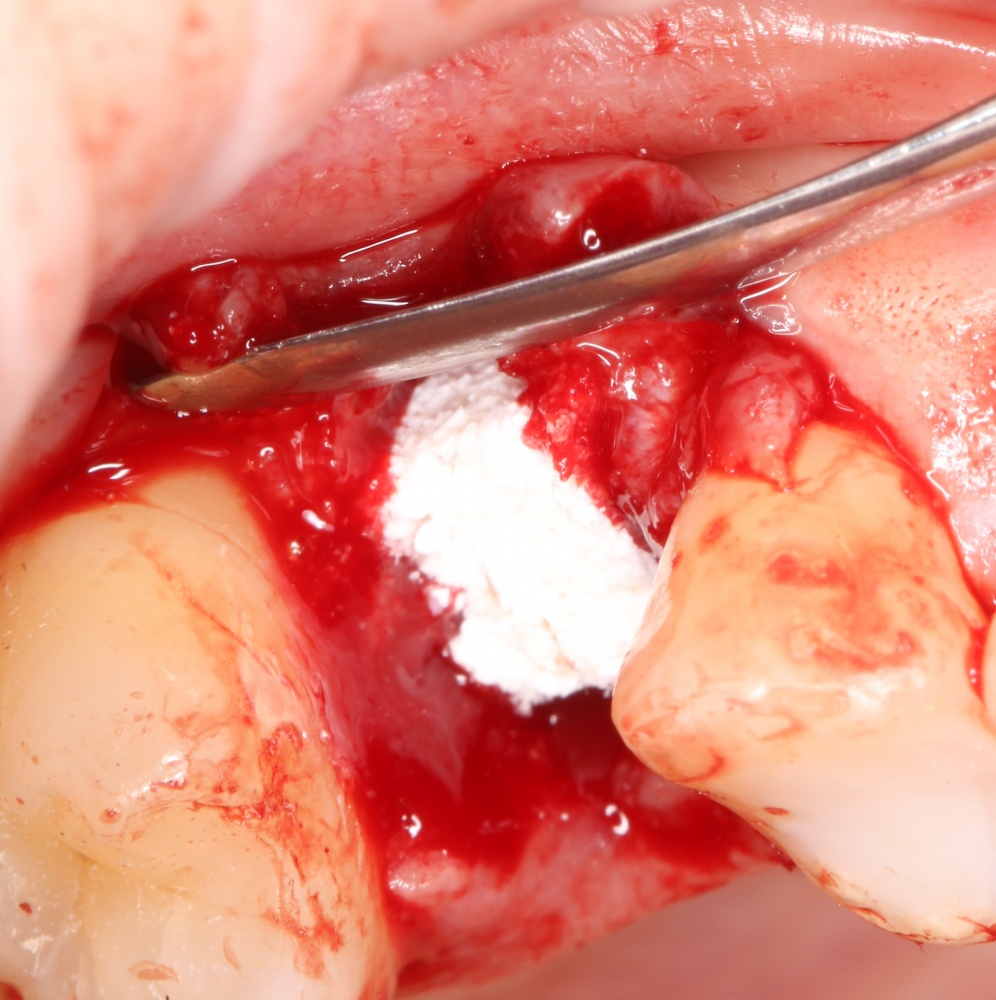

Изоляция области аутографта и имплантатов барьерной мембраной.

Перекрывать костный блок барьерной мембраной или оставить так? По этому вопросу есть много мнений. Между тем, в публикации по методике есть ясное показание, когда это требуется.

Конкретно в этом клиническом случае между костным аутотрансплантатом, ложем и имплантатами есть пустое пространство. Если его не изолировать от мягких тканей, они прорастут и осложнят интеграцию аутографта. Поэтому я решил перекрыть костный блок барьерной мембраной, пусть это делает хирургическую операцию немного дороже.

На этом этапе есть несколько нюансов, о которых я хочу рассказать отдельно.

— я использовал барьерную мембрану Geistlich Bio-Gide, которая имеет две разные поверхности: с одной стороны она рыхлая «адгезивная», с другой — гладкая и прочная. Как укладывать — на результат не влияет, но в плане удобства рыхлую поверхность мы «приклеиваем» к тому, на чем требуется барьерную мембрану удержать. В данном случае хотелось бы удержать её на костной поверхности — следовательно, мы укладываем её рыхлой поверхностью к кости.

Ремарка: примечательно, что во время синуслифтинга ситуация иная - там требуется удержать барьерную мембрану на слизистой оболочке верхнечелюстной пазухи. Следовательно, рыхлая поверхность - на стороне шнайдеровой мембраны.

— много лет мы используем антибиотики для интраоперационной профилактики инфекционно-воспалительных осложнений. Уже в то время мы пришли к выводу, что удобнее всего — порошки антибактериальных препаратов для приготовления раствором: дешевые, стерильные, в удобной упаковке. Прямо в виде порошка их можно добавлять в графт, растворы для ирригации, либо использовать так, как показано на фото. Еще мы используем порошок антибиотика для изготовления пасты, которой обрабатываем имплантаты в процессе ревизии или при лечении периимплантита. Это удобнее и эффективнее, чем интраоперационное использование жидких форм антибактериальных препаратов.

— ты знаешь, что барьерная мембрана может выполнять две функции, каркасную и изолирующую. Первая функция требует обязательной фиксации и натяжения, вторая — нет. В нашем случае «каркасом» регенерата является костный блок, а барьерная мембрана нужна только для изоляции. Поэтому она не требует натяжения и фиксации пинами.

После я внимательно проверил, что костный блок и имплантаты полностью перекрыты. Теперь рану можно ушивать.